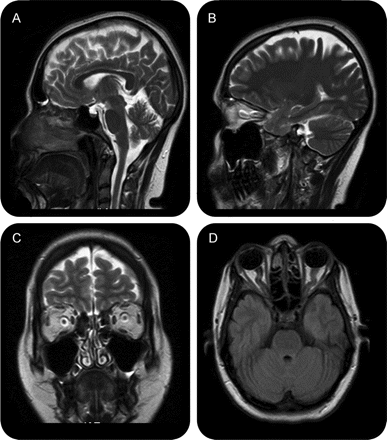

教学神经图片:特发性颅内高血压

核磁共振特性